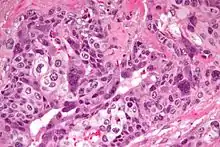

| Micrograph of choriocarcinoma showing both of the components necessary for the diagnosis – cytotrophoblasts and syncytiotrophoblasts. The syncytiotrophoblasts are multinucleated and have a dark staining cytoplasm. The cytotrophoblasts are mononuclear and have a pale staining cytoplasm. H&E stain. | |

Characteristic feature is the identification of intimately related syncytiotrophoblasts and cytotrophoblasts without formation of definite placental type villi. Since choriocarcinomas include syncytiotrophoblasts (beta-HCG producing cells), they cause elevated blood levels of beta-human chorionic gonadotropin.

Syncytiotrophoblasts are large multi-nucleated cells with eosinophilic cytoplasm. They often surround the cytotrophoblasts, reminiscent of their normal anatomical relationship in chorionic villi. Cytotrophoblasts are polyhedral, mononuclear cells with hyperchromatic nuclei and a clear or pale cytoplasm. Extensive hemorrhage is a common finding.